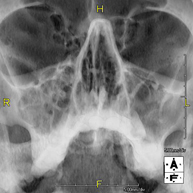

- RX Senos Paranasales

Técnica mediante la cual, utilizando rayos X, se obtienen imágenes de los senos paranasales para su estudio. Indicaciones: dificultad respiratoria nasal, tos crónica, cefalea, mucosidad.